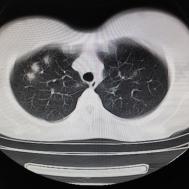

性别:女,年龄:26岁,低热,轻微胸痛,支原体阳性

[影像描述]

两肺内及胸膜下多发斑片状高密度影,部分病灶密度较淡,部分实变,边缘可见渗出改变。